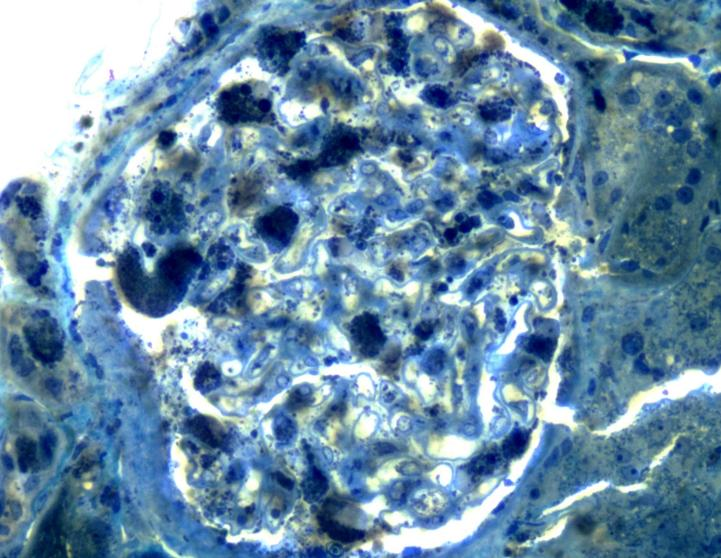

电镜表现

电镜标本经甲苯胺蓝染色,可见1个肾小球,可见嗜甲苯胺蓝颗粒在足细胞、小管上皮细胞以及壁层上皮细胞多部位沉积;

甲苯胺蓝×200,可见嗜甲苯胺蓝颗粒在足细胞、小管上皮细胞以及壁层上皮细胞多部位沉积

电镜下具有特征性改变,即肾脏各种细胞的细胞质内均可充满嗜锇“斑马小体”。(以上两张图组)

该“斑马小体”呈较高电子密度,圆形或卵圆形,直径1~5um,小体内部呈层状,层间距较一致,形似斑马皮,亦似洋葱皮、层状结构或髓鞘样结构,故称“斑马小体”“洋葱皮小体”“片层样小体”或“髓样小体”,当该小体被包含在溶酶体中,周围由一层膜包绕,为Fabry病特征性表现。(以上两张图组)

各种细胞的细胞质内均可见,包括肾小球脏层上皮细胞、壁层细胞、肾小管上皮细胞、肾间质细胞、血管壁内皮细胞和平滑肌细胞(以上六张图组)

光镜:肾小球上皮细胞肿胀伴空泡变性、泡沫细胞形成(神经鞘脂沉积);甲苯胺蓝染色可见嗜甲苯胺蓝颗粒在足细胞、小管上皮细胞以及壁层上皮细胞多部位沉积。